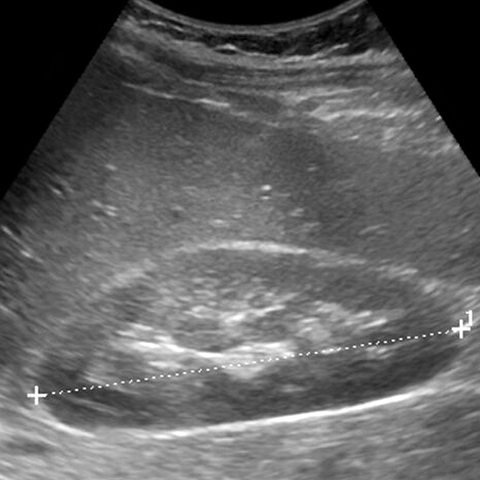

Normal kidney, Sagittal view (Ultrasound)